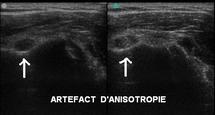

L’examen échographique des structures fibrillaires (tendons) ou lamellaires (ligaments) nécessite une attention toute particulière liée à ce qu’on appelle l’artefact d’anisotropie.

Cet artefact peut être résumé de la façon suivante :

- Si les ultrasons n’arrivent pas de façon strictement perpendiculaire au tendon, l’image correspondante apparaissant à l’écran sera faussement hypoéchogène et le tendon ne sera pas facilement reconnaissable

- Si on modifie la direction du faisceau ultrasonore pour bien l’orienter perpendiculairement au tendon, la zone hypoéchogène cèdera sa place à une image échogène fibrillaire caractéristique du tendon.